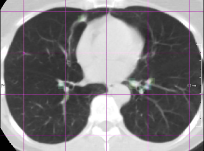

with 𝒙Fsubscript𝒙𝐹\bm{x}_{F} and 𝒙Msubscript𝒙𝑀\bm{x}_{M} the corresponding landmark locations. Based on the idea that the registration error is smooth, we include voxels from a small local neighborhood around the landmarks to increase the total set of available landmarks. In this small neighborhood we assume that the registration error is equal to the error at the center of the neighborhood. This assumption seems reasonable for smooth transformations and within a small region. The neighborhood size is chosen as 10×10×7.5mm10107.5mm10\times 10\times 7.5\;\mathrm{mm}, which is approximately equivalent to the final grid spacing of the B-spline registration (see Fig. 5).

Refer to caption

() Ground truth

(a) Predicted error

(b) Magnification of (a)

(c) Magnification of (b)

Figure 5: Example data from the SPREAD dataset. The left column (a,c) shows the fixed image with the ground truth registration error overlaid in color. The square boxes around each landmark are given the same error as the error at the landmark. The right column (b,d) shows the moving image after registration with the registration error predicted by the proposed method overlaid in color. (c) and (d) are zoomed in versions of (a) and (b).